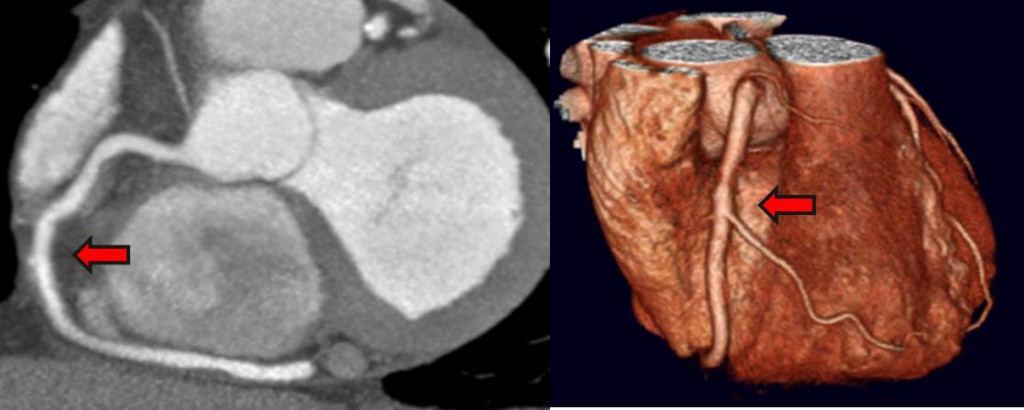

سی تی آنژیوگرافی قلب